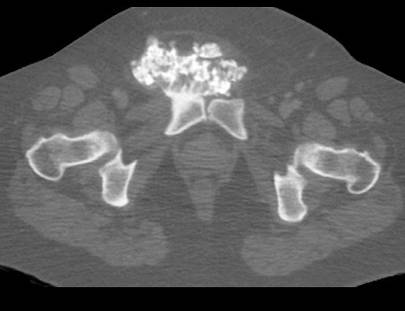

Chondrosarcoma